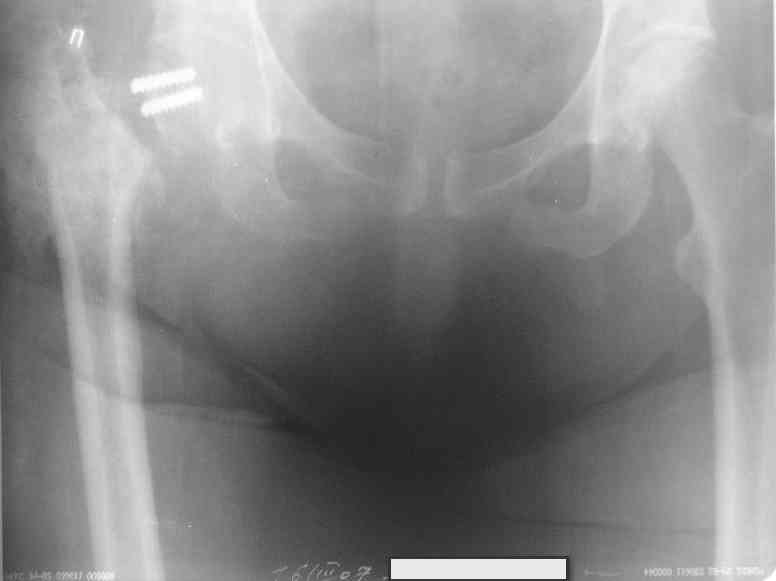

Относительно молодая женщина(39 лет), поступила в клинику в марте 2005 года, через 3 месяца после травмы с Неправильно срастающимся поперечным межвертельным переломом правого бедра. Был выполнен закрытый интрамедуллярный остеосинтез правого бедра канальным реконструкционным стержнем ChM. Ожидали бОльших проблем на операции, результату обрадовались. Как оказалось, зря. Сращение наступило через 3,5 месяца после операции.

В ноябре 2005 года произошел перелом шейки бедра и винтов в ней. В апреле 2006 импланты были удалены. В приложении фото и рентгенограммы больной. Сопутствует ожирение 4 ст. (при росте 168 см., вес больной 140кг.), сахарный диабет II тип. Имеется медиальная неустойчивость коленного и голеностопного суставов, при нагрузке колено вальгируется на 15-20 градусов.